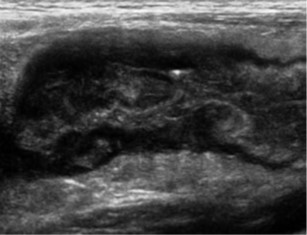

Ultraschalluntersuchungen / Sonografie

Ultraschalluntersuchungen des Bauchraumes

Konventionelle Sonografie

Farbkodierte Duplexsonografie

Ultraschalluntersuchungen der Gefäße

Vorsorge Bauchaortenaneurysma

Scherwellenelastographie der Leber (2D, Point-shear-wave) [IGeL]